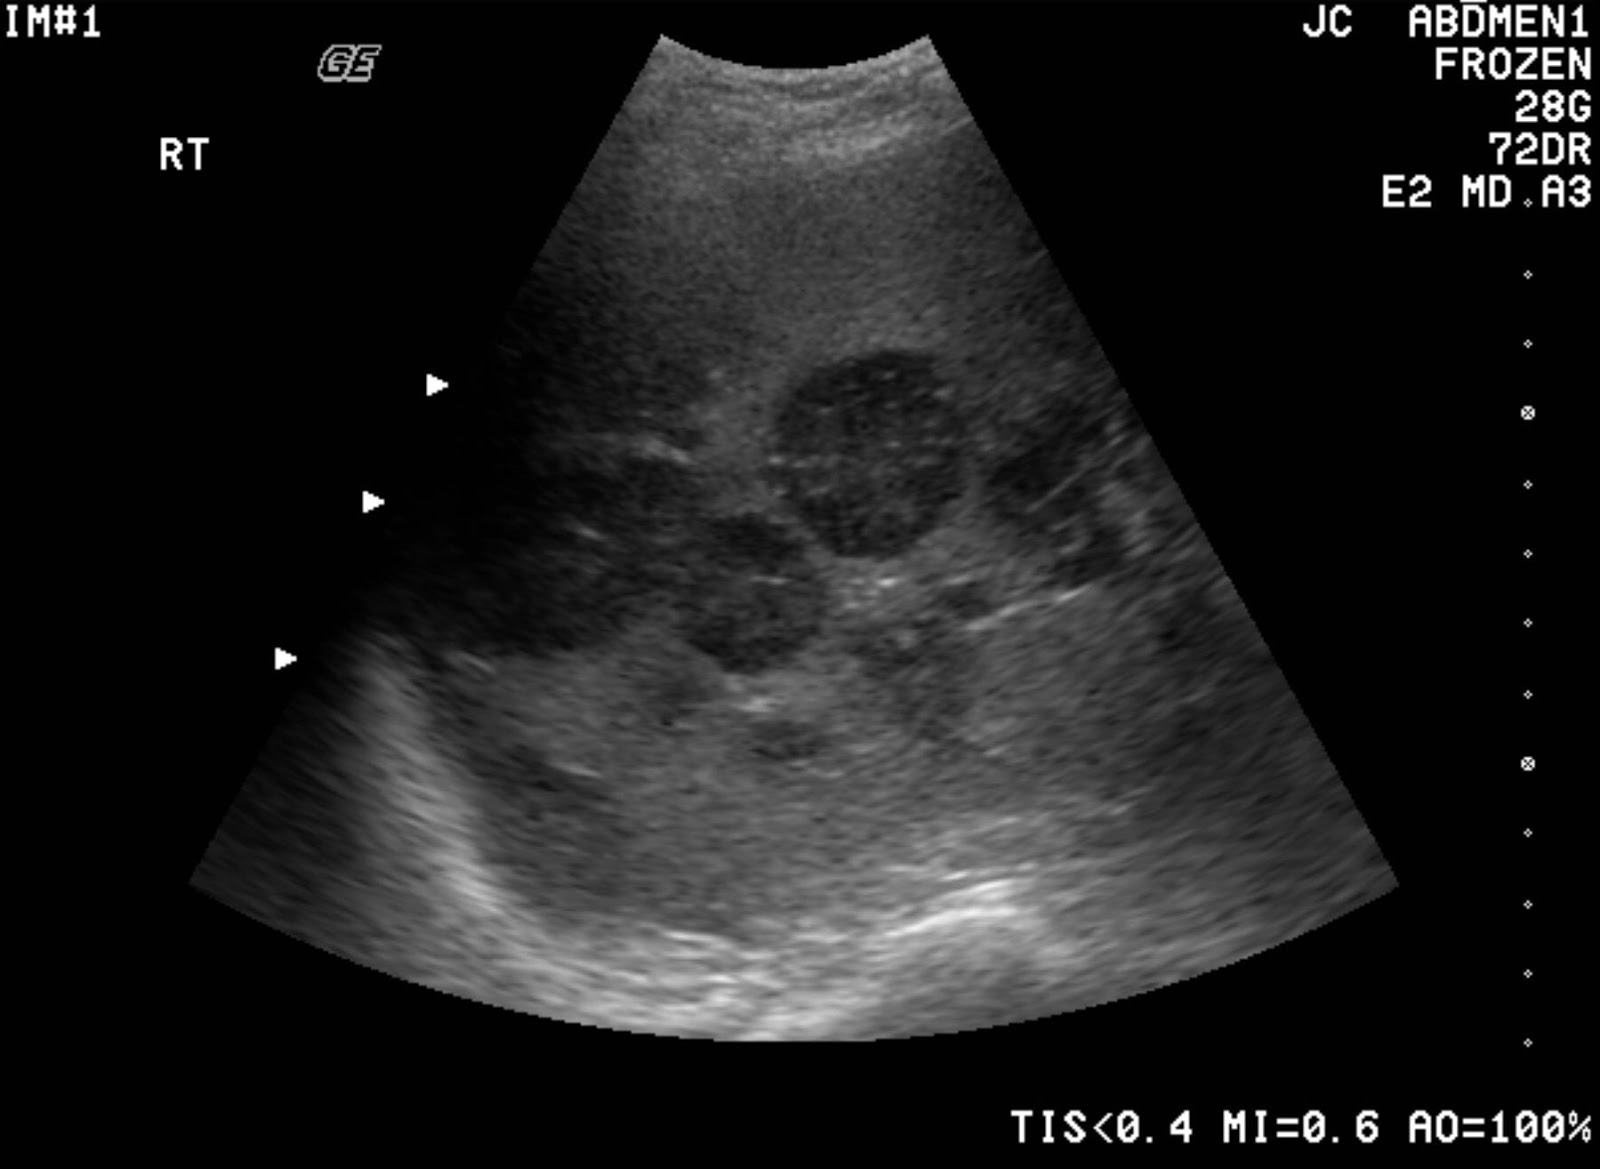

Polycystic liver disease, ultrasound scan Stock Image C017/8021 Liver Failure Ultrasound A liver ultrasound can help diagnose various conditions that affect the liver, such as. Cirrhoses) is the common endpoint of a wide variety of chronic liver disease processes which. These can lead to liver failure and. a liver ultrasound is an essential tool that helps doctors see your liver and its blood vessels in real time. a liver. Liver Failure Ultrasound.

Acute autoimmune hepatitis mimicking metastatic liver disease A case Liver Failure Ultrasound Cirrhoses) is the common endpoint of a wide variety of chronic liver disease processes which. a liver ultrasound can show signs of fat storage in your liver (steatotic liver disease), inflammation and swelling (hepatitis), and. a liver ultrasound is a noninvasive test that produces images of a person’s liver and its blood vessels. a liver ultrasound is. Liver Failure Ultrasound.